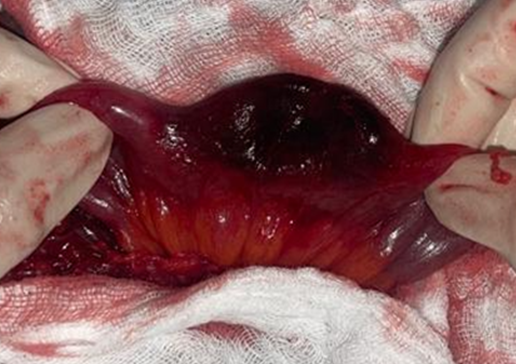

The patient was positioned supine under spinal anesthesia. Following surgical field preparation, a right inguinal incision was performed. Opening of the hernial sac revealed necrosis of the antimesenteric border of a small-bowel loop (Figure 1).

Figure 1: Intraoperative image showing necrosis of the antimesenteric border of a small-bowel loop.

Resection of the necrotic small-bowel segment was performed, followed by a hand-sewn end-to-end small-bowel anastomosis. The hernial contents were then reduced into the abdominal cavity, and the hernial sac was resected after closure. Finally, repair of the right femoral hernia was carried out using the McVay technique with non-absorbable sutures.

Histopathological examination of the resected specimen demonstrated necrotic and hemorrhagic changes, confirming the diagnosis of ischemic intestinal injury secondary to hernial strangulation.